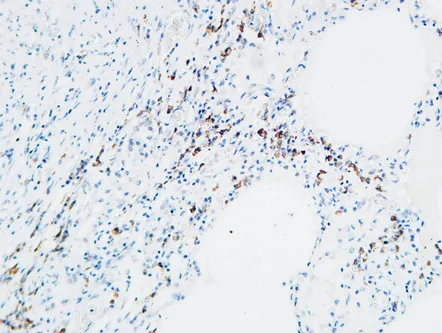

MPO Rabbit Polyclonal Antibody

Cat: APRab14056

Size1:50μl Price1:$118

Size2:100μl Price2:$220

Size3:500μl Price3:$980

Size2:100μl Price2:$220

Size3:500μl Price3:$980